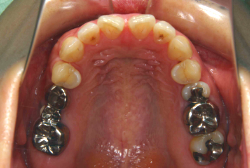

急速拡大装置を1日1回装置の中央にある拡大ネジを、ご自身で回して頂くことで25日間くらいかけて、6mmほど拡大しました。拡大後は、上顎の前歯の隙間が広がっていることがお分かりいただけると思うのですが、土台の骨ごと広がるのでこのような隙間ができます。その後1年半くらいマルチブラケット装置を使用して、全体の修正を行いました。

結局、歯の本数を減らすことなく、すべてご自分の歯を残して正しい配列にすることができました。このケースの場合、2009年10月より拡大と経過観察を行い、2012年3月より1年2ヶ月マルチブラケット装置を装着、2013年5月に治療を終了しました。2段階で行う治療としては短期間で終了しているケースと思います。